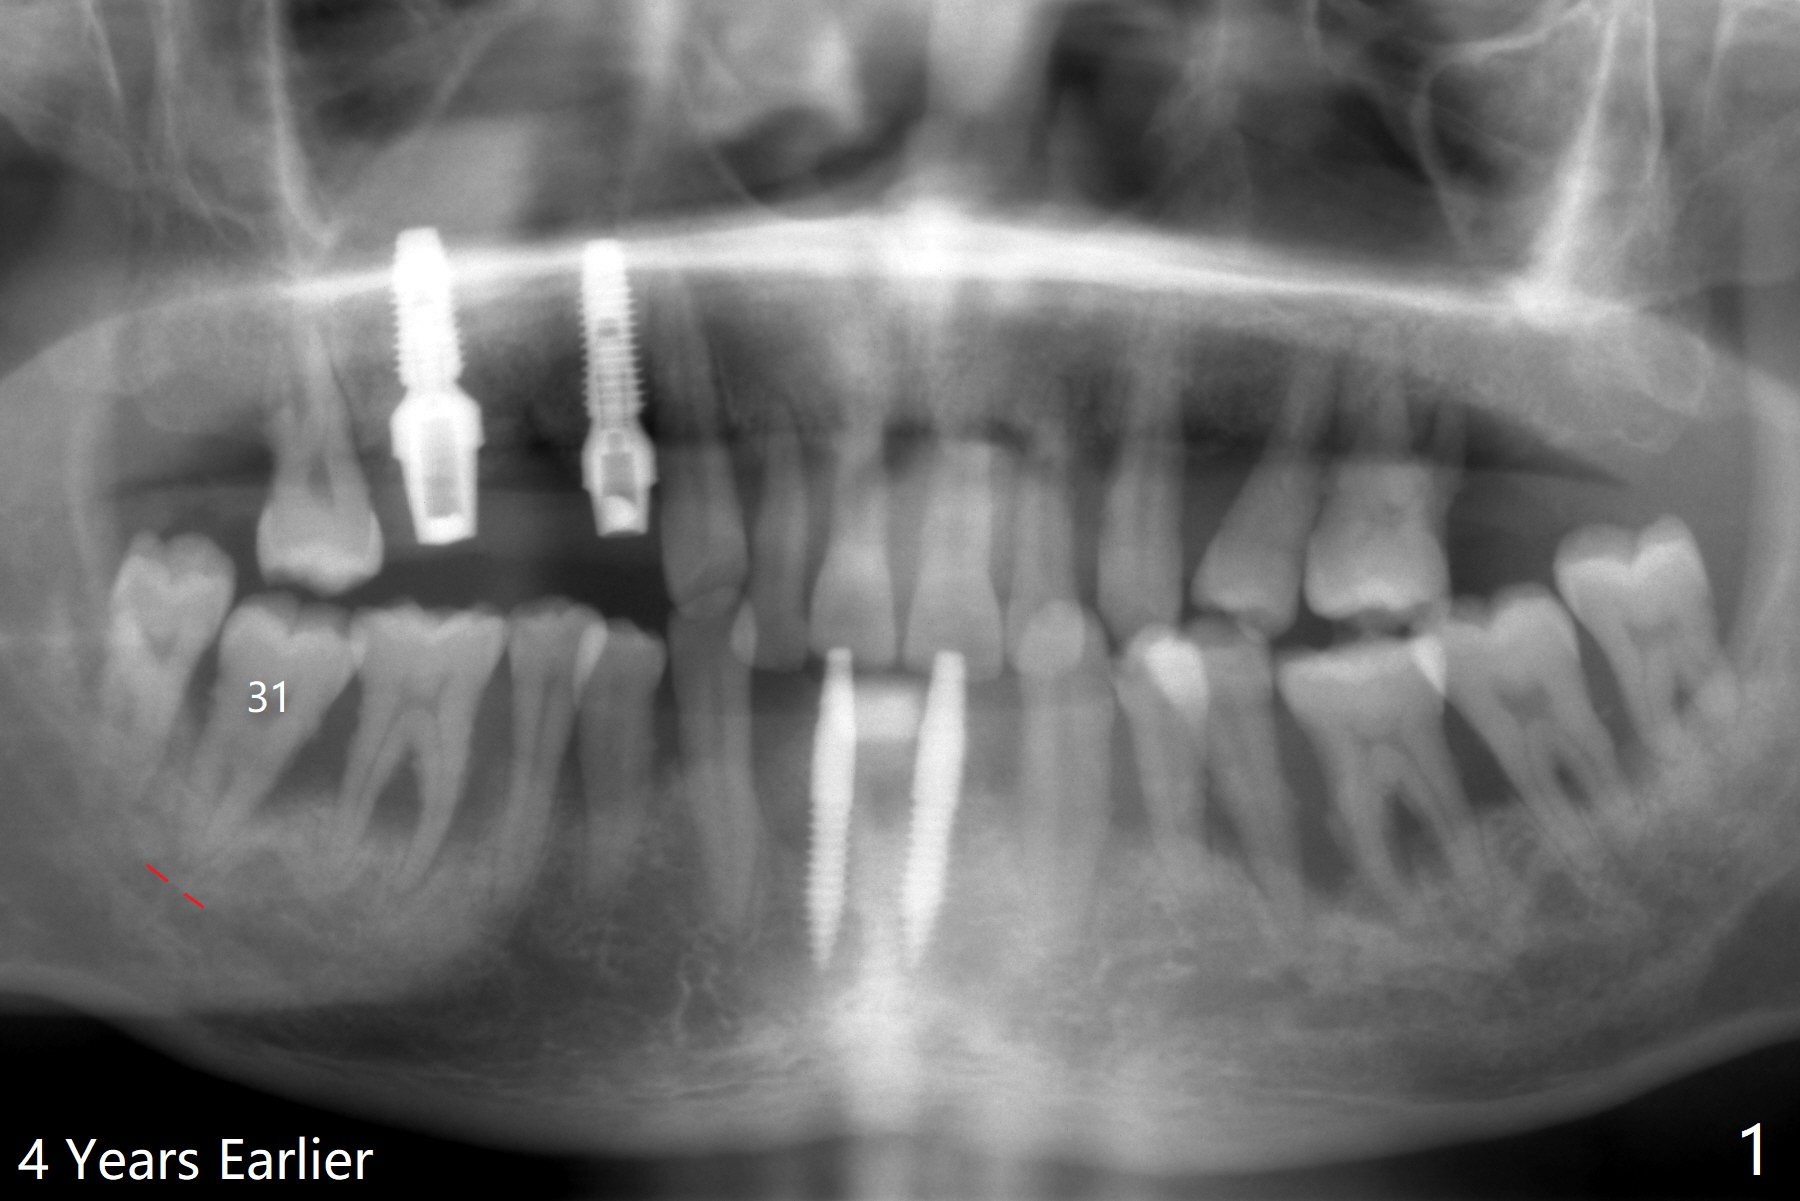

40岁男,牙周炎(图一,4年前拍摄),现在要求拔除31号牙,劝导后同意植骨,问题在于牙根长(图二),可能接近神经(红虚线)。拔牙后,舌侧骨板缺失,不敢大胆在根尖清创,术中拍摄根尖片(图三),牙槽窝根尖接近神经管,最后可能遗留些根尖肉芽组织(图四:*(最好拍摄CT))。粘性骨粉表面覆盖PRF和Cytoplast,使用4-0 PTFE缝线,没有使用牙周敷料,因为后者往往与缝隙粘连,脱落时缝线必须撤除,可能影响不可吸收膜固定。不过这次不可吸收膜术后四天脱落,术后五天骨粉好像丢失不多(图五),可能与粘性骨粉有关。下次需要牙周敷料,牙齿长,敷料固定好。Return to Protect Graft 19 位点保存 Xin Wei, DDS, PhD, MS 1st edition 06/28/2021, last revision 07/09/2021